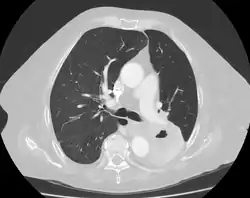

A lung cavity or pulmonary cavity is an abnormal, thick-walled, air-filled space within the lung.[1] Cavities in the lung can be caused by infections, cancer, autoimmune conditions, trauma, congenital defects,[2] or pulmonary embolism.[3] The most common cause of a single lung cavity is lung cancer.[4] Bacterial, mycobacterial, and fungal infections are common causes of lung cavities.[5] Globally, tuberculosis is likely the most common infectious cause of lung cavities.[6] Less commonly, parasitic infections can cause cavities.[5] Viral infections almost never cause cavities.[7] The terms cavity and cyst are frequently used interchangeably; however, a cavity is thick walled (at least 5 mm), while a cyst is thin walled (4 mm or less). The distinction is important because cystic lesions are unlikely to be cancer, while cavitary lesions are often caused by cancer.[3]

Diagnosis of a lung cavity is made with a chest X-ray or CT scan of the chest,[2] which helps to exclude mimics like lung cysts, emphysema, bullae, and cystic bronchiectasis.[5] Once an imaging diagnosis has been made, a person’s symptoms can be used to further narrow the differential diagnosis. For example, recent onset of fever and productive cough suggest an infection, while a chronic cough, fatigue, and unintentional weight loss suggest cancer or tuberculosis.[2] Symptoms of a lung cavity due to infection can include fever, chills, and cough.[5] Knowing how long someone has had symptoms for or how long a cavity has been present on imaging can also help to narrow down the diagnosis. If symptoms or imaging findings have been present for less than three months, the cause is most likely an acute infection; if they have been present for more than three months, the cause is most likely a chronic infection, cancer, or an autoimmune disease.[5]